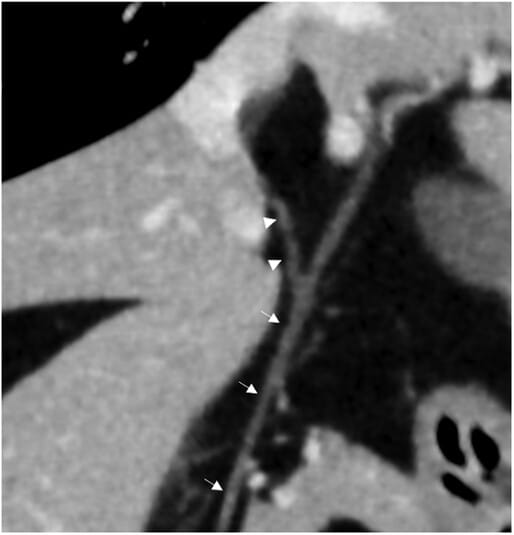

Multiplanar reconstruction of a dog where only the right lateral divisional bile duct (RLD—arrowheads) is visible that inserts into the common bile duct (CBD –slim arrows). CT image was reconstructed with a soft tissue algorithm, matrix 512 × 512, slide thickness 1.25 mm, 120 kV, 220 mA, pitch 0.562